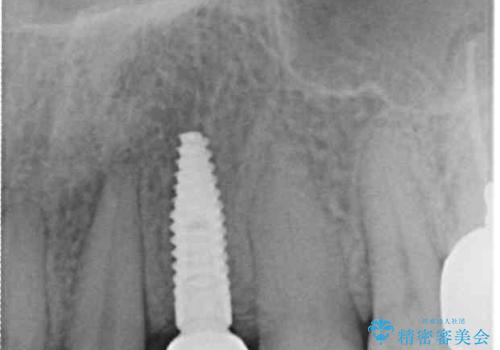

左上は後続永久歯の欠損によりスペースがあり、矯正治療と並行してインプラントあるいはブリッジによる補綴治療が必要な状況でした。

矯正治療と並行してインプラントによる補綴治療を行うこととしました。

矯正治療が終わるタイミングに合わせてインプラントの埋入を行っていたので、矯正治療を終了すると同時にセラミック補綴治療を行えました。